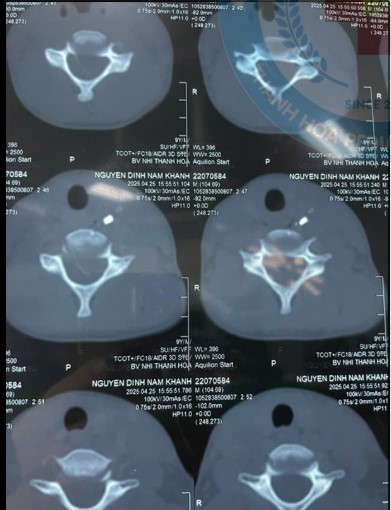

| Mảnh kính đâm vào cổ bé trai được lấy ra - Ảnh BVCC |

Rất may mắn, kíp mổ đã thuận lợi lấy ra mảnh kính vỡ, không còn tác nhân đe dọa đến tính mạng, sức khỏe của trẻ. Sau phẫu thuật, trẻ tiếp tục được theo dõi, chăm sóc tích cực tại khoa Tai mũi họng bệnh viện.